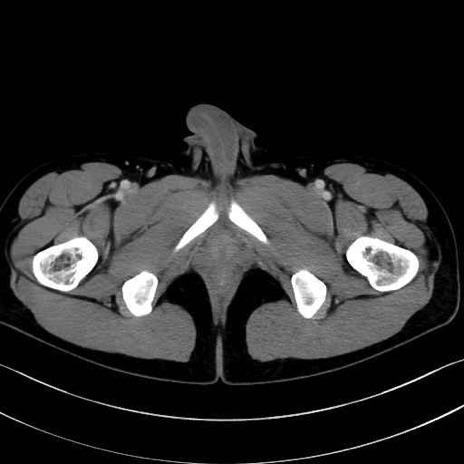

大内転筋(Adductor magnus)、小内転筋(Adductor minimus) のCT画像の解剖

大内転筋・小内転筋 (Adductor magnus / Adductor minimus)